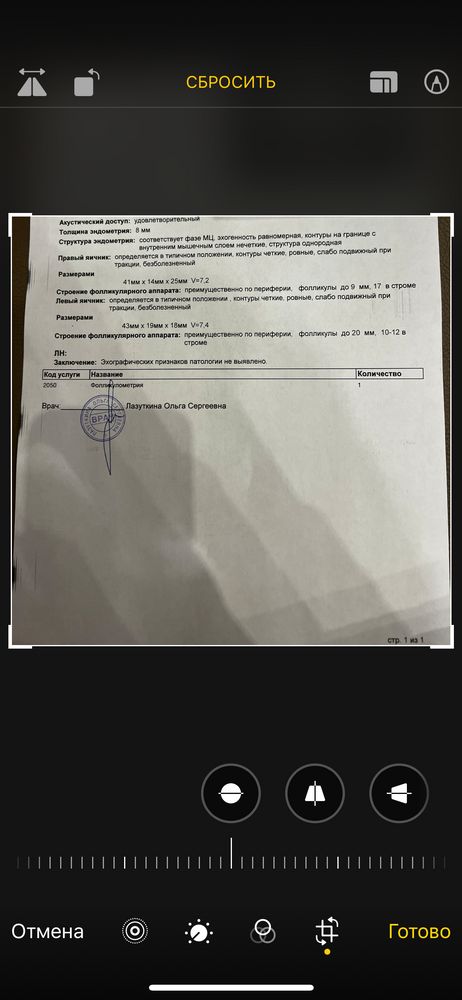

Всем доброго дня. Может ли быть такое, что сразу после овуляции (а может даже в момент) не будет свободной жидкости?

узист сказала может. И что похоже овуляция как раз вот она.

а Репродуктолог сказала, что нет. И скорее всего овуляция не произошла , а произошла лютеинизация.